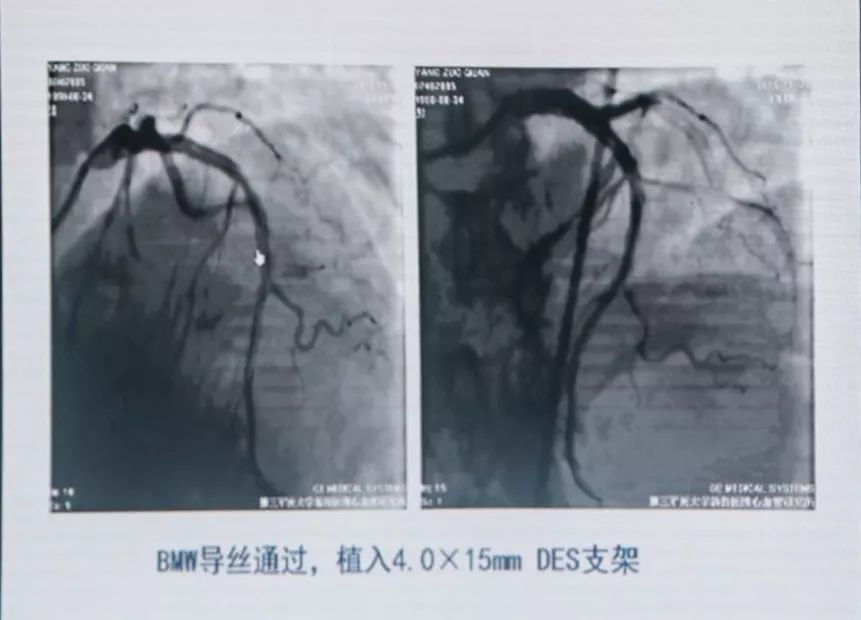

有条件者应尽快进入导管室行急诊冠状动脉造影,以多体位投照明确无夹层及支架膨胀不良。若血管完全闭塞,待球囊扩张部分血流恢复后再行造影。应尽快使导丝通过血栓病变,建议应用软头导引导丝。

支架内血栓形成可能与支架未充分贴壁有关。可用短于支架长度的高压球囊再次PTCA。若造影确认血栓形成可能与支架近或远端内膜撕裂、支架未完全覆盖病变有关,可再次置入支架,观察20 min后,若患者胸痛缓解、血压及心电监测稳定、TIMI血流III级,可视为成功。但应注意,除非有证据显示血栓形成与上述因素相关,否则不可再次置入新支架。Dutch研究发现,首次出现支架血栓的患者,再次置入新支架,发生支架血栓的风险比未置入新支架的患者增加4.2倍。